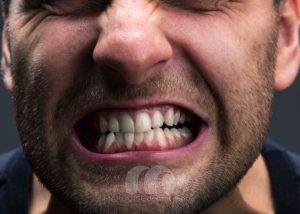

دندان قروچه

🦷 دندان قروچه چیست؟ درمان دندانقروچه در کلینیک دندانپزشکی مارکیز 💎 دندان قروچه یا براکسیسم یکی از مشکلات شایع دندانپزشکی است که معمولاً شبها و در هنگام خواب رخ میدهد. فرد بدون اینکه متوجه باشد، دندانهای خود را محکم روی هم فشار میدهد یا به هم میساید. این کار در طولانیمدت میتواند باعث سایش دندانها، شکستگی دندان، درد عضلات فک و حتی مشکلات مفصلی فک (TMJ) شود. در کلینیک دندانپزشکی مارکیز با استفاده از روشهای تخصصی، علت دندان قروچه بررسی شده و بهترین روش درمان برای هر بیمار ارائه میشود. 💎 🔍 علائم دندان قروچه اگر یک یا چند مورد از این علائم را دارید، احتمال زیادی وجود دارد که دندان قروچه داشته باشید: 🚨 سایش و صاف شدن سطح